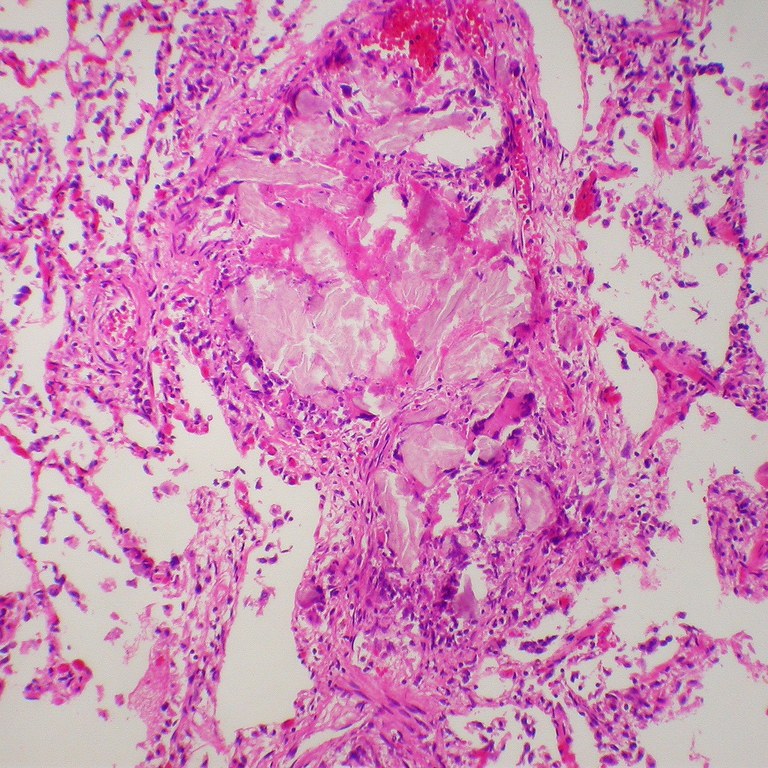

- “Microcrystalllne cellulose – Foreign body pulmonary embolization in an intravenous drug abuser” by Y. Rosen, MD is licensed under CC BY-SA 2.0